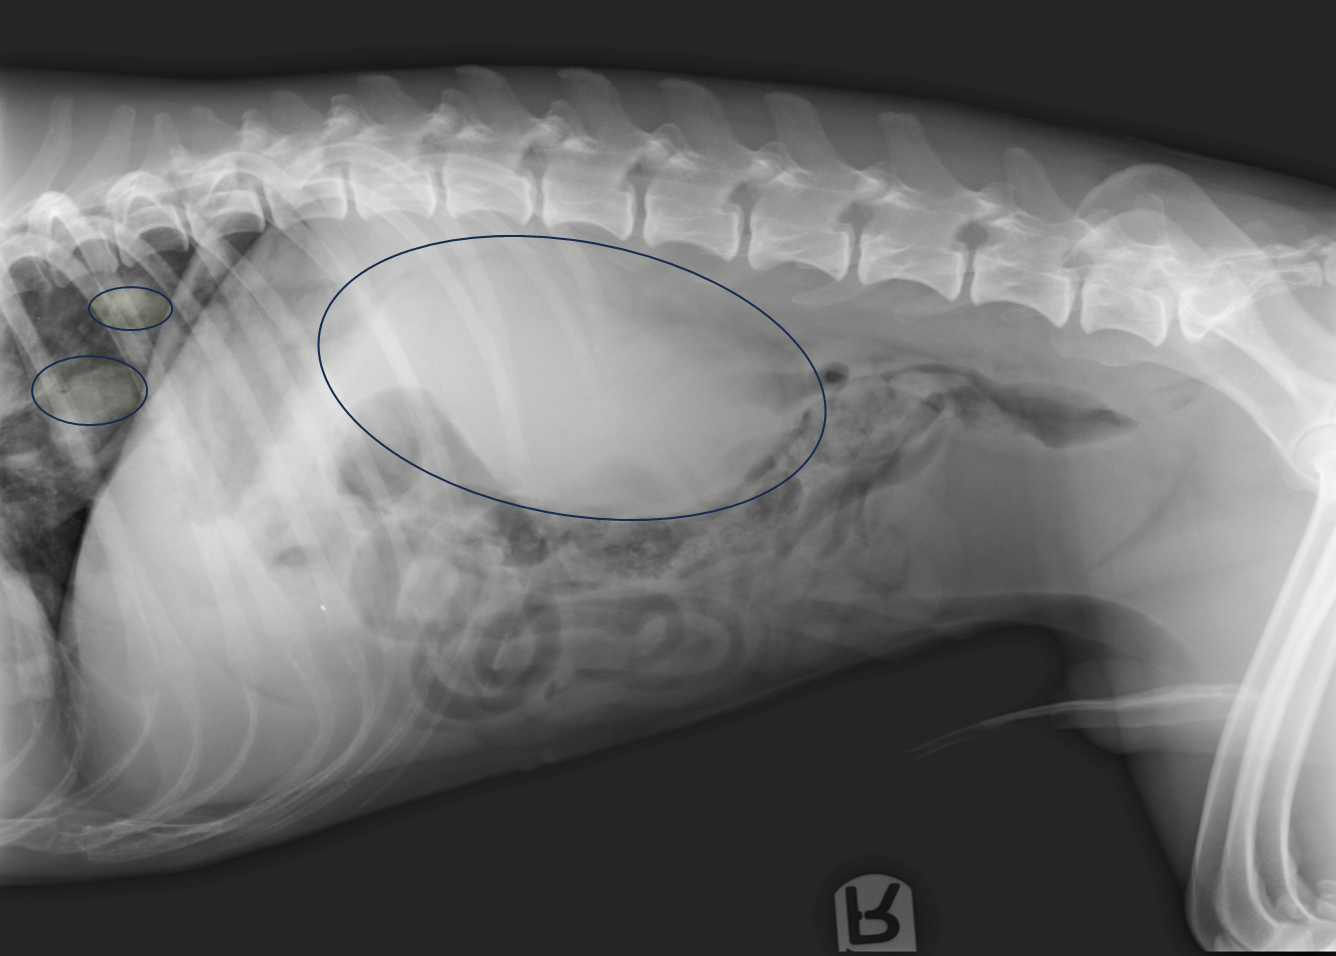

What is being shown on this radiograph?

Mineralised calculi opacities present within the bladder lumen

Urethra has been collimated out of the radiograph —> retake radiograph to see if mineralised calculi is along length of urethra